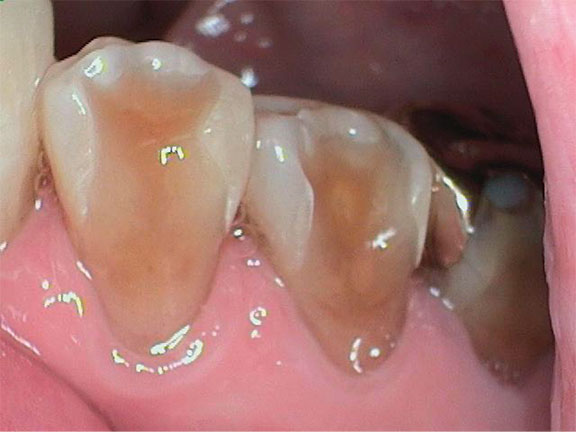

Severe buccal erosion, Nos. 28 and 29. Note shadow of pulp chambers.

Figure 4

Biomechanical: Significant tooth structure loss had occurred between 2009 and 2017 (Figure 1 through Figure 3). Severe attrition had occurred on the anterior teeth, especially tooth No. 11. Severe erosion and abrasion were present on teeth Nos. 11, 18, 20, 21, 28, 29, 31, and 32 (Fig-

ure 4). The patient had generalized sensitivity, and tooth No. 18 was painful due to deep erosion, which approached the pulp chamber. Teeth Nos. 7 and 10 had moved out of position and rotated (Figure 5). The progression of erosion over the 8-year period could also be seen radiographically and was especially noticeable on tooth